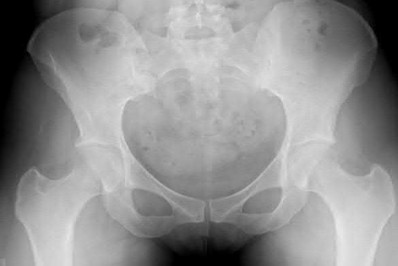

Question 11:

A poly-trauma patient presents hemodynamically unstable with an anteroposterior compression (APC-III) pelvic ring injury. A circumferential pelvic binder is requested to reduce pelvic volume and control hemorrhage. To be anatomically effective, the binder must be centered precisely over which of the following landmarks?

Options:

- Iliac crests

- Anterior superior iliac spines

- Greater trochanters

- Ischial tuberosities

- Symphysis pubis

Correct Answer: Greater trochanters

Explanation:

For optimal mechanical advantage and effective reduction of an 'open book' pelvic fracture (APC type), a pelvic binder must be applied directly over the greater trochanters of the femurs. Applying it higher, such as over the iliac crests, is a common error that fails to adequately close the pelvic ring and can paradoxically open the true pelvis.